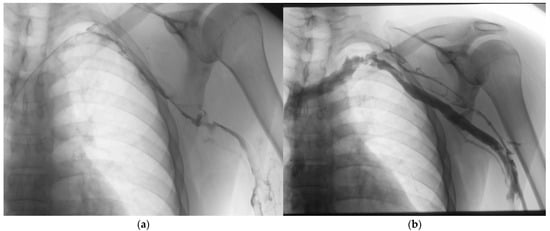

4.1. Catheter-Directed Thrombolysis

4.1.2. Adjunctive Techniques

4.4. Venous Stenting

4.4.1. Indications and Technical Considerations